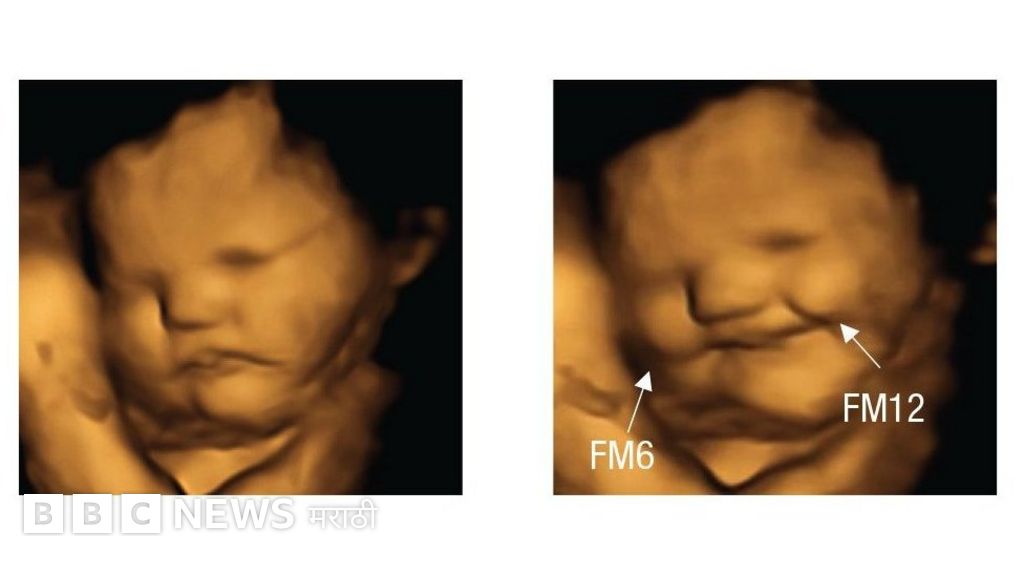

आईने गाजर खाताच गर्भातील भ्रूणाचा चेहरा हसरा होतो. तर हेच भ्रूण कडवट चवीची पालेभाजी खाल्ल्यानंतर त्याला नापसंती दर्शवत असल्याचंही या प्रयोगातून दिसून आलं आहे.

या अहवालानुसार, त्यांनी गरोदर महिलांना गोळ्या खाण्यासाठी दिल्या होत्या. त्याच्या 20 मिनिटांनंतर त्यांनी या महिलांच्या पोटाचं अल्ट्रासाऊंडमार्फत निरीक्षण केलं.

फोटो स्रोत, Fetal and Neonatal Research Lab, Durham University

यामध्ये गोड चवीची गोळी खालेल्या महिलांच्या पोटातील भ्रूण हसत असल्यांचं तर कडवट चवीची गोळी खाल्लेल्या महिलांच्या पोटातील भ्रूण तोंड वेडंवाकडं करत असल्याचं स्पष्टपणे दिसून आलं.

त्याचवेळी इतर 30 महिलांच्या पोटातील भ्रूणांचंही निरीक्षण करण्यात आलं. त्यावेळी, या भ्रूणांच्या चेहऱ्यावर कोणत्याच प्रकारचे हावभाव दिसले नाहीत, हे विशेष.